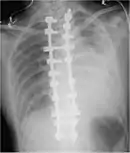

CT scan of the chest showing a hemothorax caused by warfarin use

Computed tomography (CT or CAT) scans may be useful for diagnosing retained hemothorax as this form of imaging can detect much smaller amounts of fluid than a plain chest X-ray. However, CT is less used as a primary means of diagnosis within the trauma setting, as these scans require a critically ill person to be transported to a scanner, are slower, and require the subject to remain supine.[23][26]